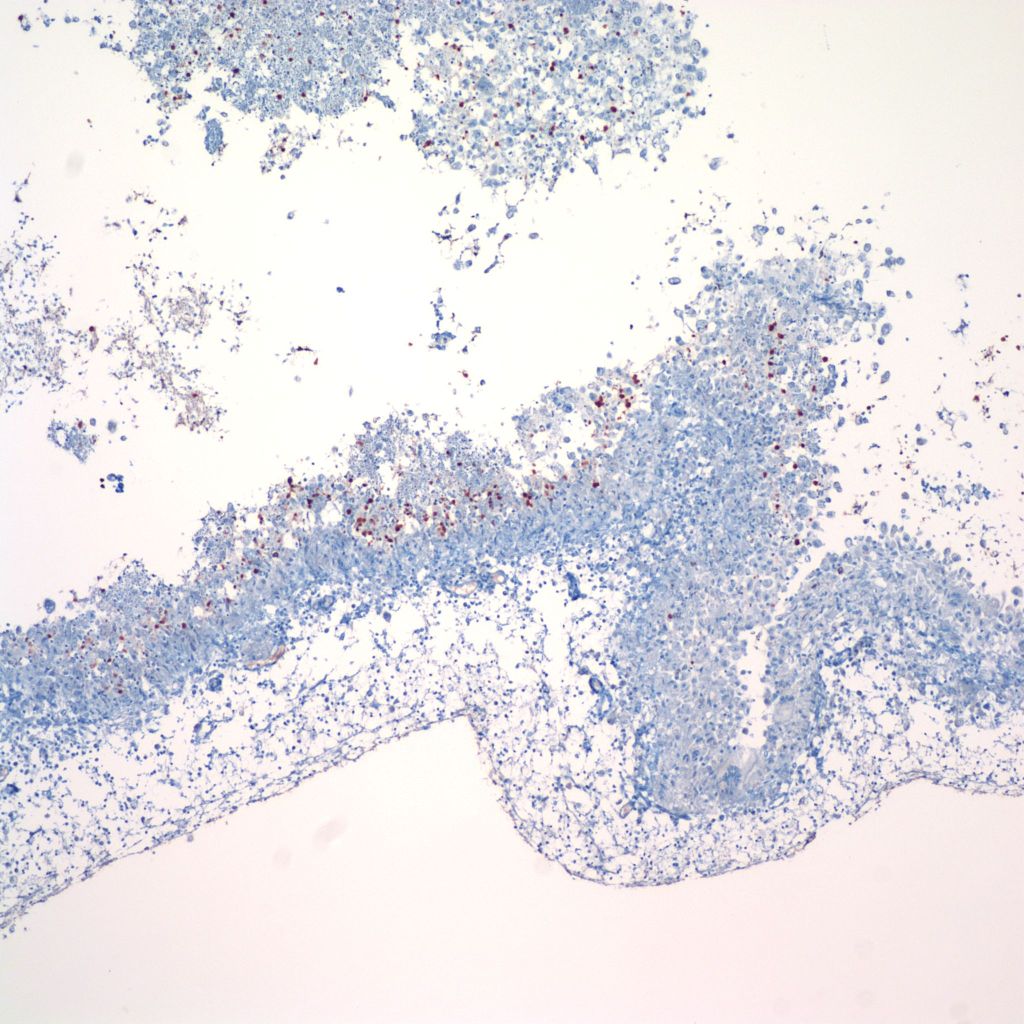

Parenchymal hemorrhages may have underlying vascular lesions that are not perceptible grossly (Fig 21a, b).